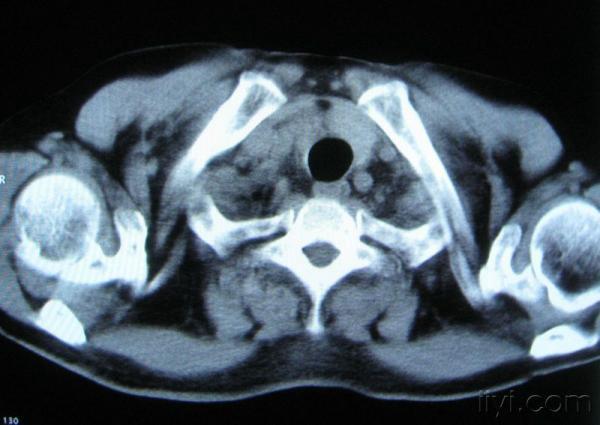

你指那个肯定是淋巴结,中央系坏死,这很常见,特别在双侧腹股沟会经常看到。这个双侧腋窝及纵隔见多发小淋巴结征。

根据位置考虑应该是淋巴结,密度不均,是因为肿大的淋巴结中心液化坏死